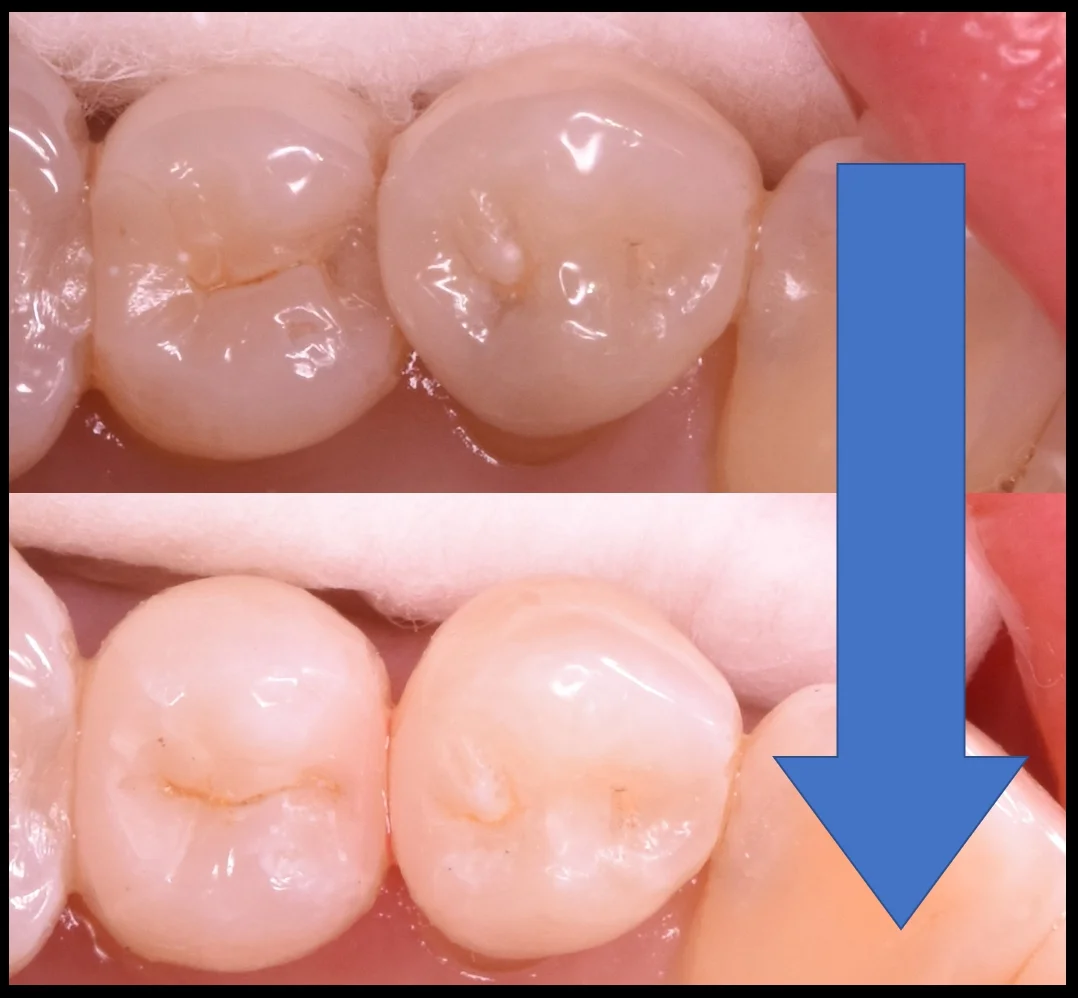

術前術後の写真がこちらになります。

ブラッシングはしやすくなったかと思いますので、これで長期予後を期待できるかと思います。

フロスも引っ掛からないようにしているので、定期的にフロスを通してもらえると良いかなって思います。